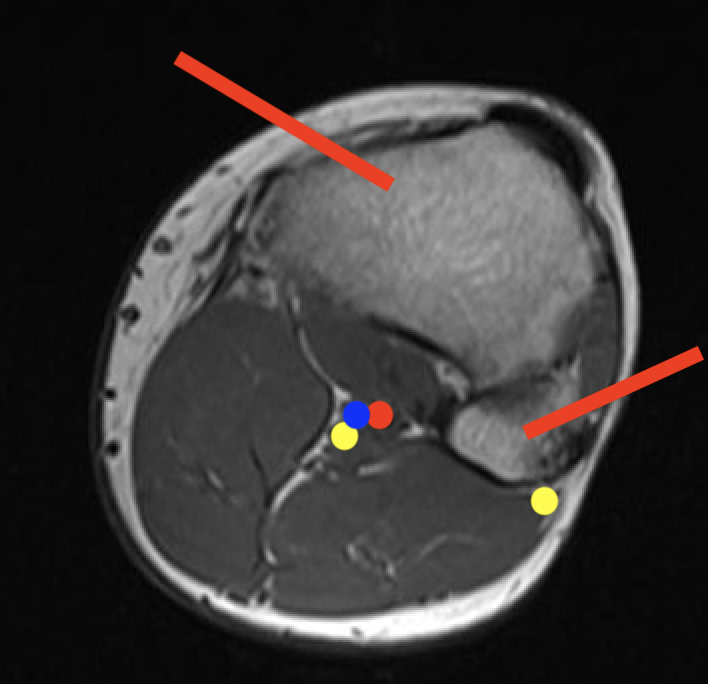

3.  Condyles

- medial: incision through vastus medialis

- lateral: anterior to vastus lateralis